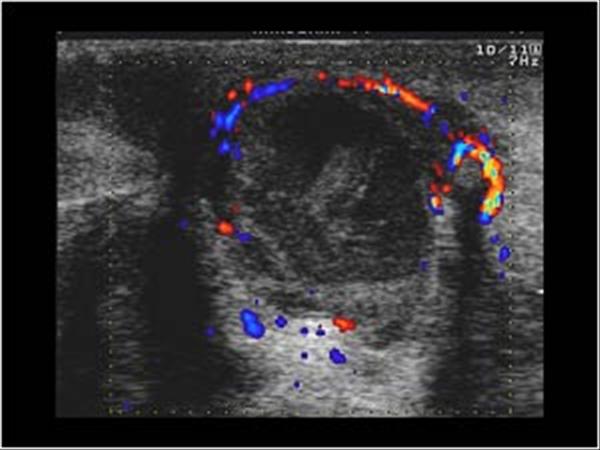

Apxe vú

Apxe vú - Ảnh 4

» Thông tin: Nữ giới – 21 tuổi.

» Lâm sàng: Sưng đau tuyến vú.